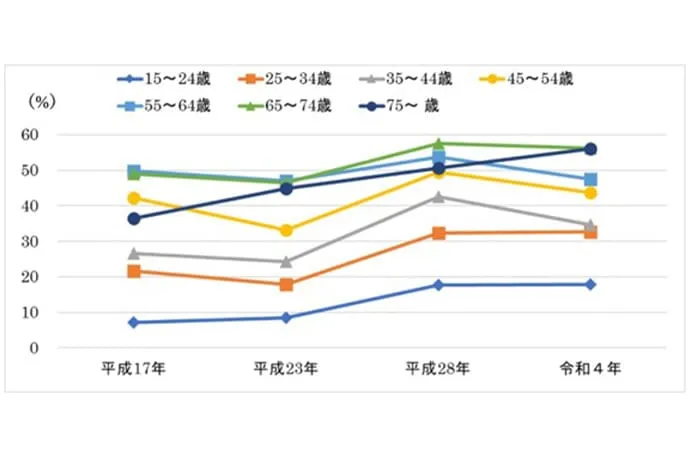

2018年の8020推進財団の調査では、歯を失う原因として最も多いのが歯周病であることが明らかになりました。また、2022年の歯科疾患実態調査によると、25歳以上の約30%が歯周病に罹患しており、45歳以上では40%以上、65歳以上では50%以上にのぼると報告されています。

令和4年歯科疾患実態調査の結果(概要)(厚生労働省)より引用

令和4年歯科疾患実態調査の結果(概要)(厚生労働省)より引用

令和4年歯科疾患実態調査の結果(概要)(厚生労働省)より引用

歯は顎の骨によって支えられています。歯と歯ぐきの間には「歯周ポケット」と呼ばれるすき間があり、健康な状態では深さは3mm以下です。

しかし、歯ぐきに炎症が起きたり、歯を支える骨が破壊されている場合には、歯周ポケットが4mm以上に深くなります。まずはこの歯周ポケットの状態を詳しく検査します。